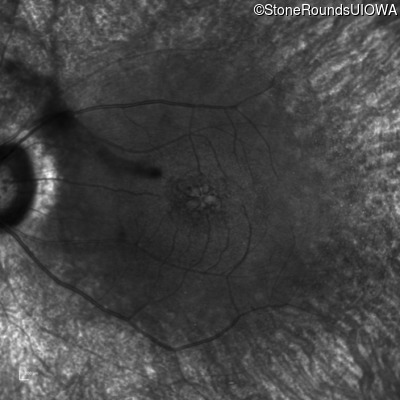

Age at visit: 49 years (Visit 2)